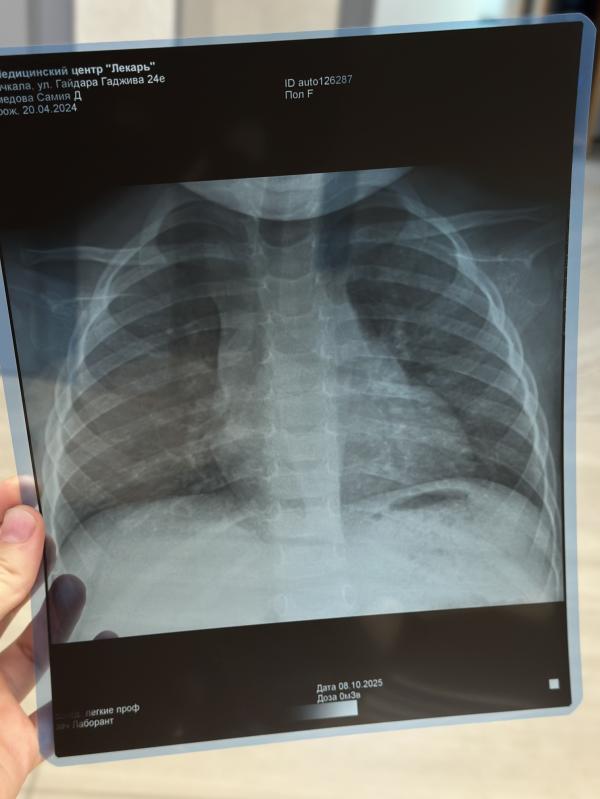

У маленькой тоже бронхит

У обоих теперь он🫠